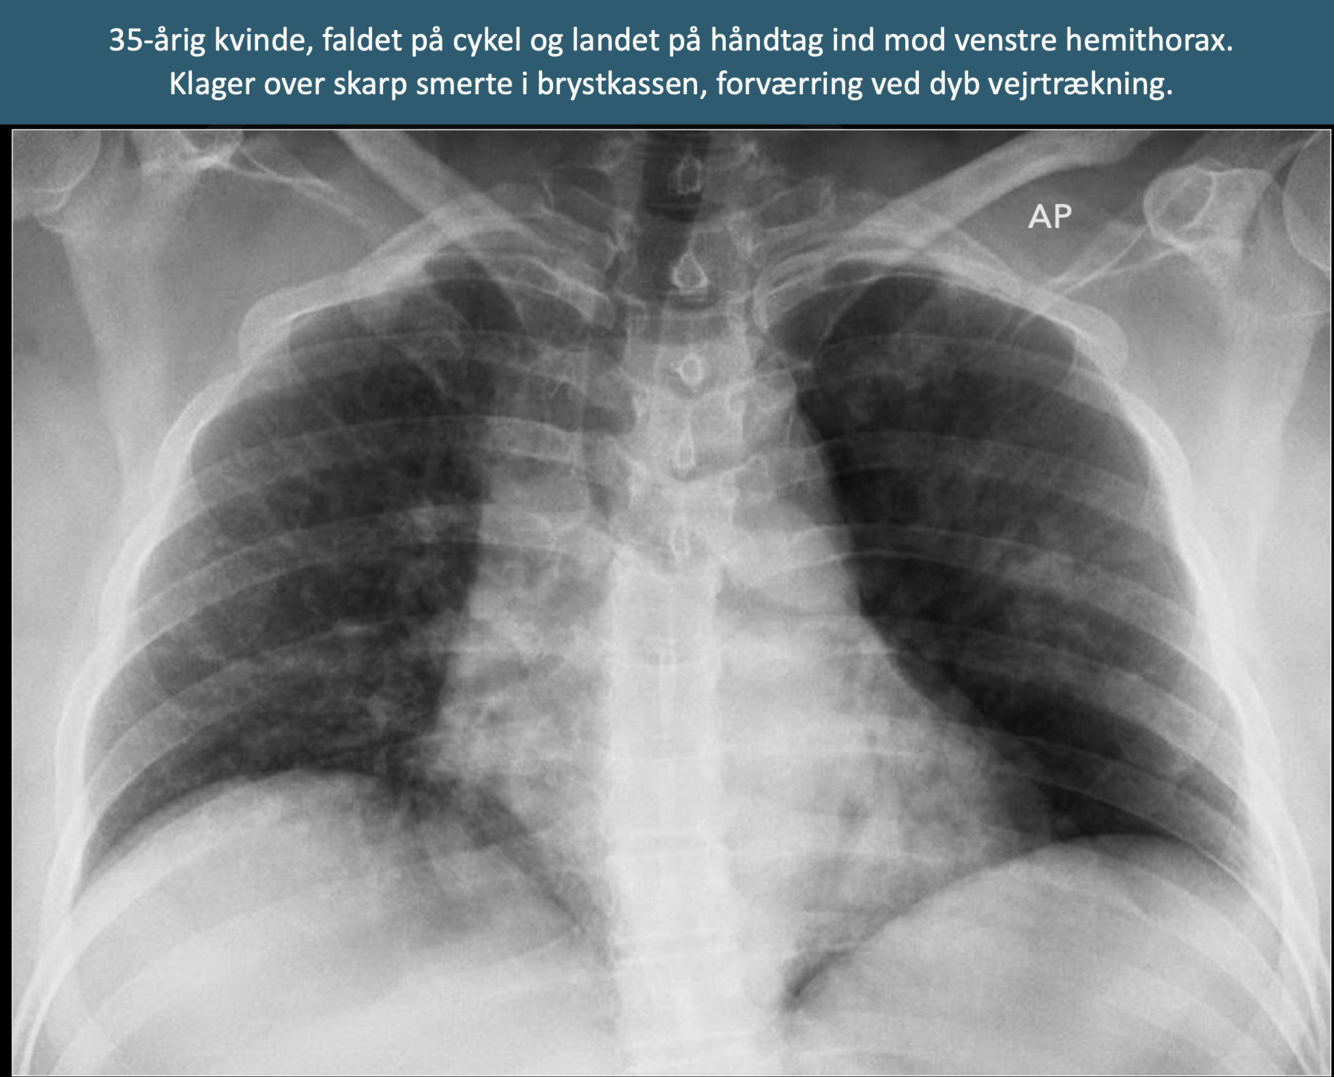

Q

Diagnose?

18

A

Tragtbryst (pectus excavatum)